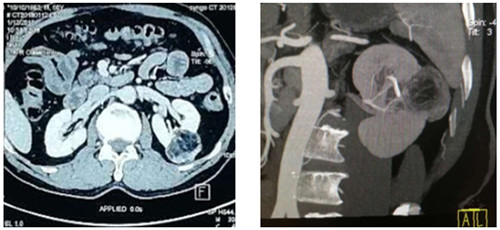

如图一图二为肿瘤位置及大小,图三即为手术操作通道(5mm、10mm、12mm),术中游离出肾动脉后,用图四的血管夹临时阻断肾脏血液供应,剜除肿瘤后,在腔镜下缝合肾脏,确定缝合严密,再恢复肾脏血供!要求阻断时间不能超过30分钟,此例患者阻断17分钟!此类手术技术难度大,腹腔镜下缝合要求高,并对血供阻断有时间要求!